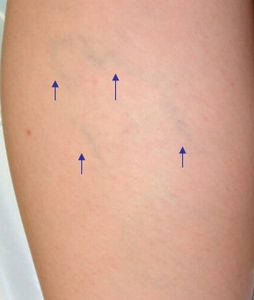

許多女生都有這類靜脈浮現的問題, 雖然不至於到"曲張", 但是也妨礙觀瞻 !! 這也是可以解決的.

許多女生都有這類靜脈浮現的問題, 雖然不至於到"曲張", 但是也妨礙觀瞻 !! 這也是可以解決的.